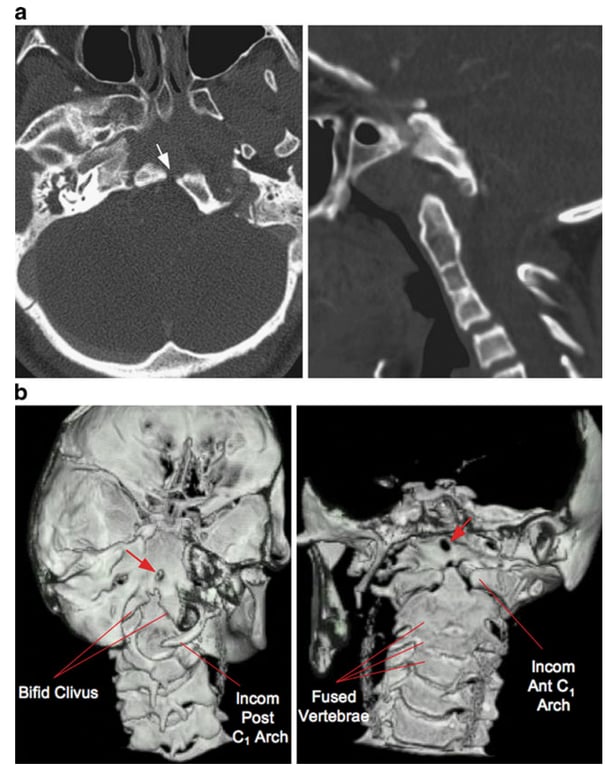

• A

• Left: Axial CT shows the gap in the lower clivus (arrow).

• Right: Sagittal CT shows the odontoid process is far anterior to its usual position below the clivus. Fusion of the C2, C3 and C4 centra is also seen.

• B, CT 3-D rendering of the skull base.

• Left: View from the back shows widely bifid basiocciput and an oval defect (arrow) higher in the clivus. The posterior C1 arch is deficient.

• Right: view from the front shows the odontoid is far forward from the bifid clivus (mostly covered by the dens), and the anterior C1 arch is also bifid. Note upper clival defect (arrow). incomplete posterior C1 arch; Incomplete anterior C1 arch